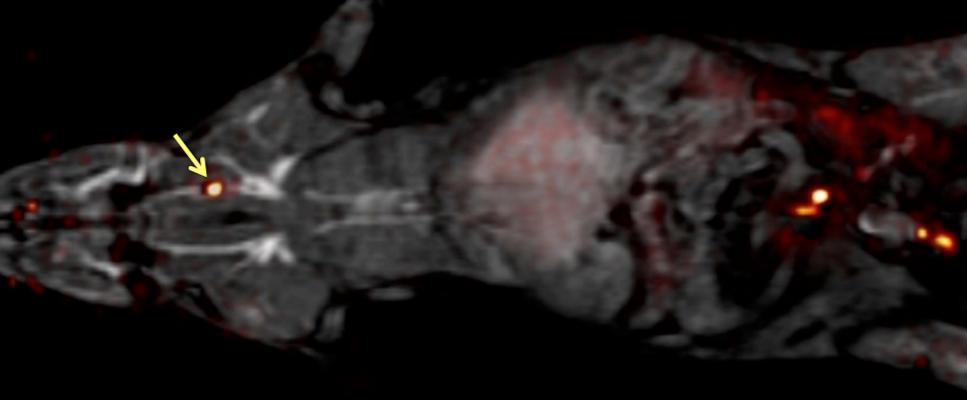

The whole body of a rat can be imaged for blood clots with one PET scan (which is overlaid here on an MRI image) using the FBP8 probe. Arrow points to a blood clot. Image courtesy of Peter Caravan, Ph.D.

The researchers first analyzed how well each probe bound to fibrin in a test tube, and then they studied how well the probe detected blood clots in rats. "The probes all had a similar affinity to fibrin in vitro, but, in rats, their performances were quite different," said Caravan. He attributed these differences to metabolism. Some probes were broken down quickly in the body and could no longer bind to blood clots, but others were resistant to metabolism. "The best probe was the one that was the most stable," he said. The team is moving into the next phase of research with this best-performing probe, called FBP8, which stands for "fibrin binding probe #8." It contained copper-64 as the radionuclide.